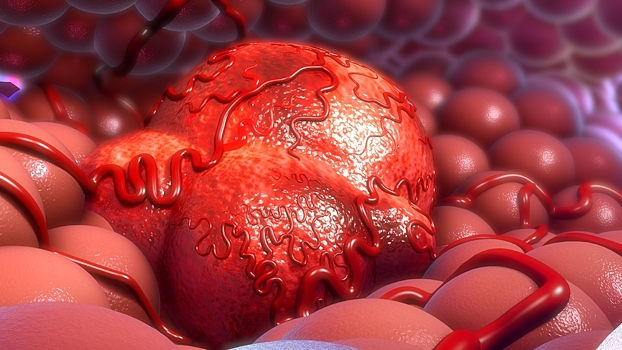

Помимо этого, возможность появлений опухолей (в частности, молочной железы, толстой кишки, пищевода, головы, шеи, мочеточников) может провоцировать излишнее потребление спиртного.